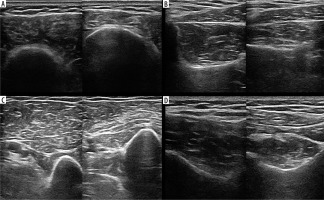

Figure 4

High-resolution ultrasound image of atrophy of the deltoid (A), biceps brachii (B), supraspinatus (C) and infraspinatus (D) muscles in a 57-year-old patient with Parsonage-Turner syndrome – right side of each section. Images obtained by author with a 5-20 MHz linear probe of the Mindray Resona I9